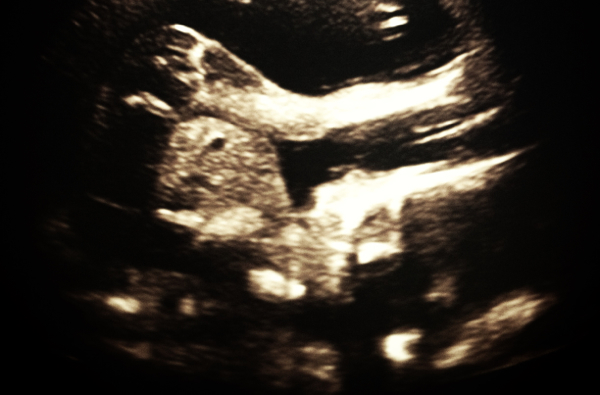

RUL i dag, Kenneth är en frisk...

...och väldigt vig liten unge. Och det här med att det ligger ett dubbelvikt barn i min mage, det är ju helt jävla overkligt - och samtidigt så himla självklart. Fan vad häftigt det är.

Och världens konstigaste känsla måste ju vara att plötsligt få reda på att man ska få en son. Ba: "Jaha, jag ska bli mamma. Till en pojke".

Plötsligt är man inte bara gravid, utan man ska få ett barn, som på grund av att han är just en han kanske ärver sin pappas längd och vackra ögonfransar, och man får plötsligt en helt annan bild av den där kommande ungen. Något slags utseende.

Oh my god. Vi ska få en son.